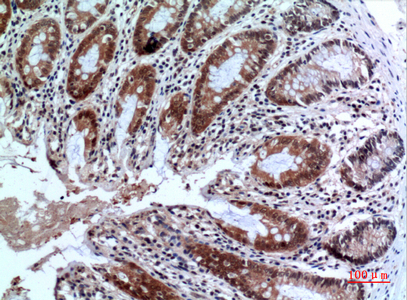

IHC 1/50-1/100 Human,Mouse,Rat

FOXP3 antibodies are essential tools for identifying and characterizing Tregs in research and clinical settings. These antibodies target specific epitopes of the FOXP3 protein, enabling its detection via techniques like flow cytometry, immunohistochemistry, and Western blotting. Due to FOXP3's intracellular localization, staining typically requires cell fixation and permeabilization. Researchers rely on FOXP3 antibodies to study Treg dynamics in diseases such as cancer, autoimmune disorders, and transplant rejection, where Treg populations often correlate with disease progression or therapeutic outcomes. Commercial FOXP3 antibodies (e.g., clones 236A/E7) are validated for human, mouse, and other model organisms, though species cross-reactivity must be confirmed. Recent efforts focus on standardizing FOXP3 antibody specificity to address variability in staining patterns across studies. As Treg-targeted therapies advance, FOXP3 antibodies remain pivotal for both mechanistic research and biomarker development.